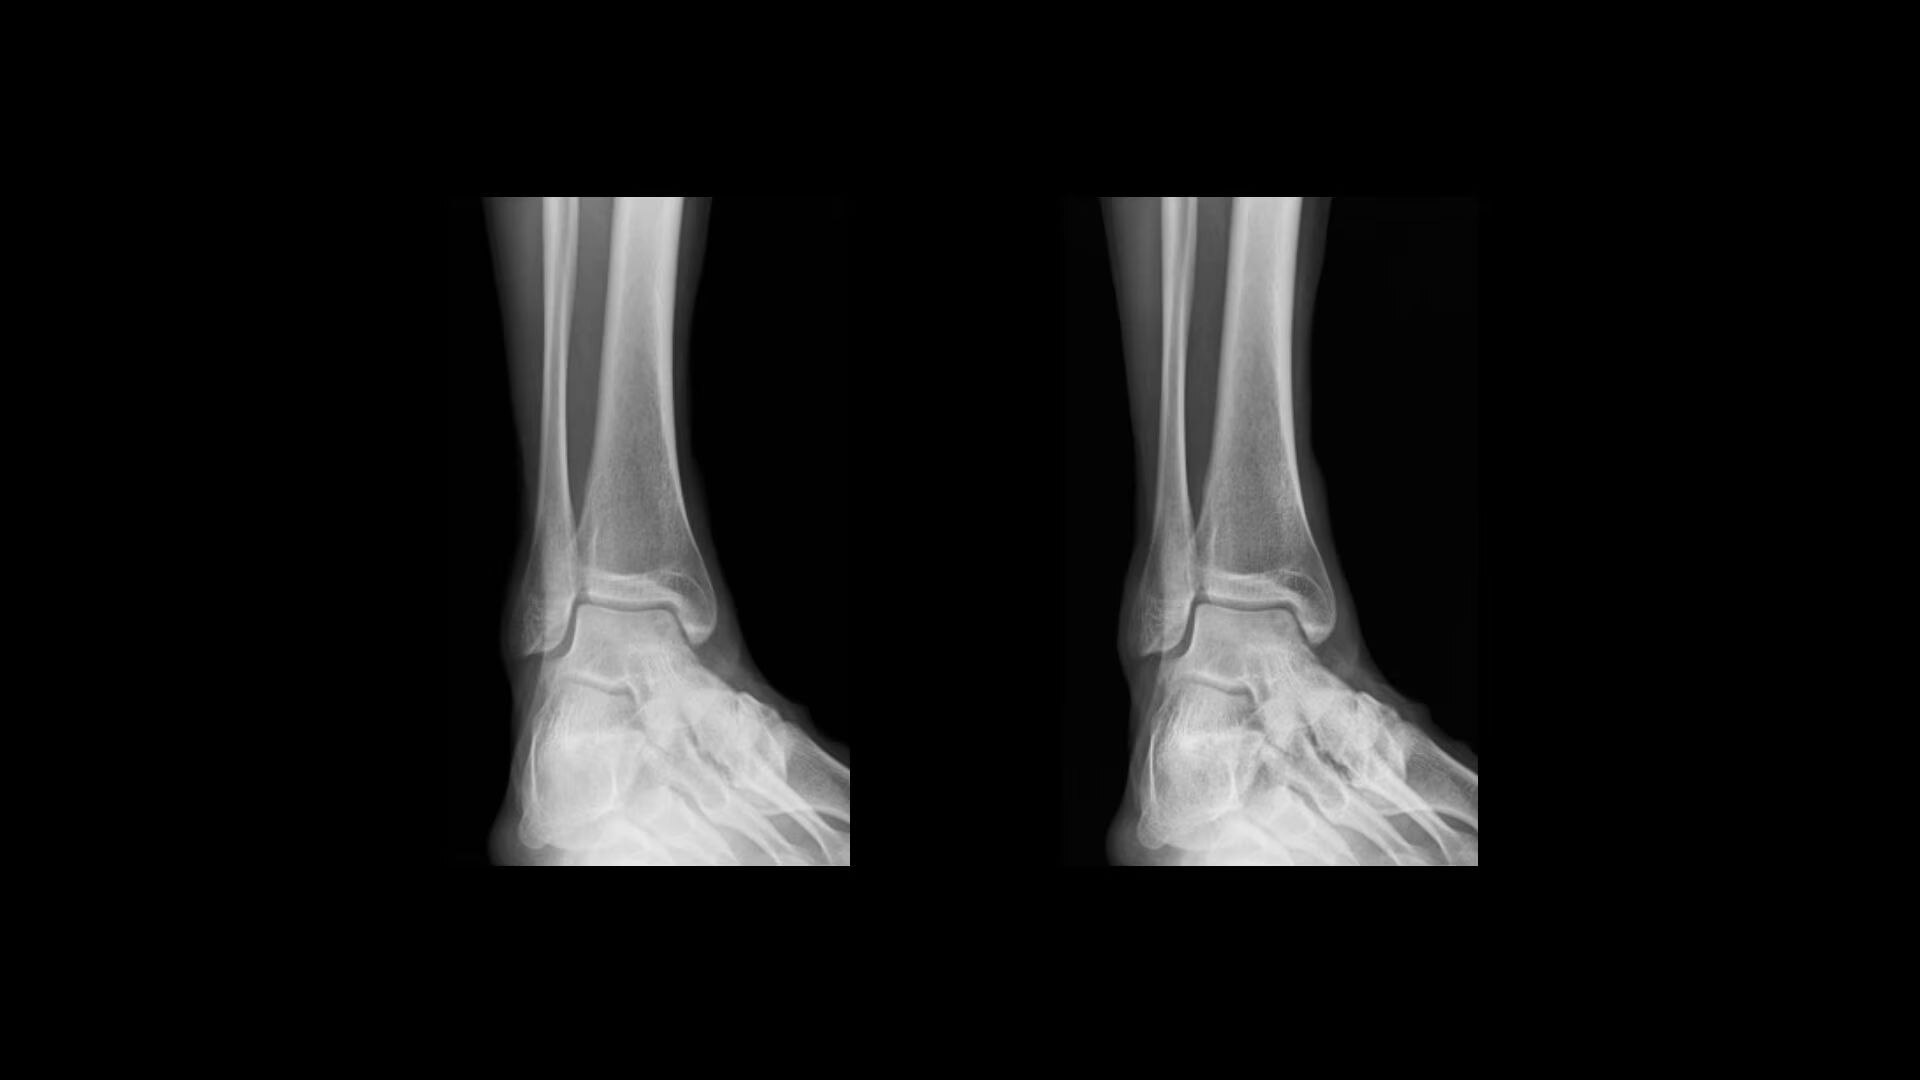

Improve visualization and detail

Local Contrast Enhancement (LCE) increases local contrast in both pediatric and adult chest X-ray images for better visualization of the lungs, heart, and spine regions. It is also available for ankle joint (AP), foot (AP), and patella (tangential)*, and has three levels of enhancement (low, medium and high).